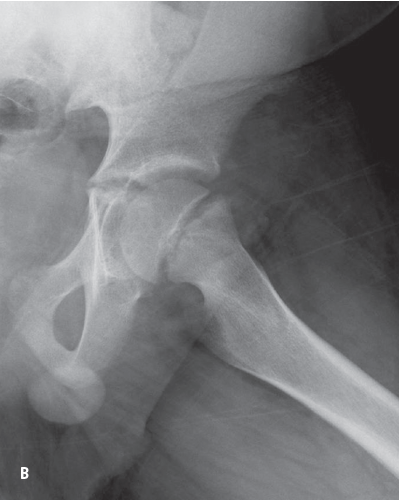

Plain radiographs showing anteroposterior views of the left hip in neutral (A) and frog-leg (B) positions lead to the diagnosis.

The radiographs show widening of the proximal femoral growth plate. A line drawn along the superior edge of the femoral neck (the Klein line) normally crosses the epiphysis. In our patient’s radiograph, however, the epiphysis falls below this line (Figure).

Figure – A radiograph of our patient’s hip shows that the femoral epiphysis lies below the Klein line.

Slipped capital femoral epiphysis (SCFE) is the posterior and inferior slippage of the femoral epiphysis over the metaphysis at the level of the physeal plate. It represents a Salter-Harris type I fracture and is characterized by widening of the physeal growth plate. It presents in children between 8 and 15 years of age, coinciding with the growth spurt of puberty.

Plain radiographs are used to diagnose SCFE. However, a negative radiography result in a child with classic findings does not rule SCFE out. A computed tomography scan is indicated in such cases.